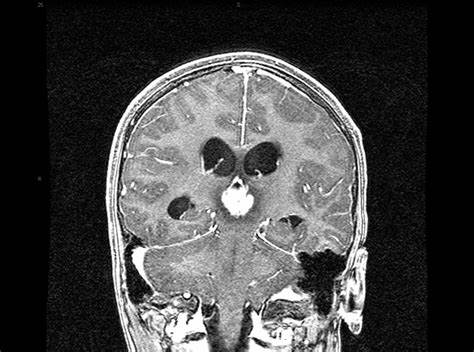

松果体瘤是在松果体中形成的肿瘤。腺体是大脑中部的小腺体。它被你的大脑包围。它产生一种称为褪黑激素的激素,会影响您的睡眠-觉醒周期。松果体肿瘤是少见的肿瘤。它们较常发生于儿童和40岁以下的成年人。 松果体区肿瘤能活多久? 相关阅读:肿瘤全切术点亮8岁松果体区肿瘤男孩生存希望

松果肿瘤并不总是癌症。但是它们在成长过程中仍然会引起问题,因为它们会挤压大脑的其他部位,并会阻塞脑脊液的正常流动。这是包围并缓冲大脑的液体。阻塞会增加颅内压(ICP),即颅骨内部的压力。